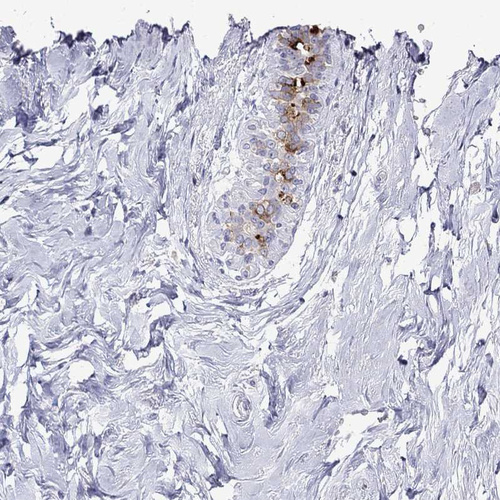

Immunohistochemical staining of human breast shows moderate cytoplasmic positivity in glandular cells.